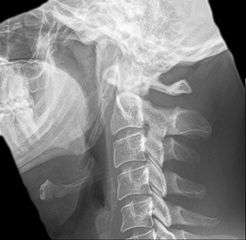

Radiograph, lateral view showing elongated stylohyoid process and stylohyoid ligament ossification

Radiograph, lateral view showing joint-like formation in ossified stylohyoid ligament

Diagnosis is suspected when a patient presents with the symptoms of the classic form of "eagle syndrome" e.g. unilateral neck pain, sore throat or tinnitus. Sometimes the tip of the styloid process is palpable in the back of the throat. The diagnosis of the vascular type is more difficult and requires an expert opinion. One should have a high level of suspicion when neurological symptoms occur upon head rotation. Symptoms tend to be worsened on bimanual palpation of the styloid through the tonsillar bed. They may be relieved by infiltration of lidocaine into the tonsillar bed. Because of the proximity of several large vascular structures in this area this procedure should not be considered to be risk free.

Imaging is important and is diagnostic. Visualizing the styloid process on a CT scan with 3D reconstruction is the suggested imaging technique.[6] The enlarged styloid may be visible on an orthopantogram or a lateral soft tissue X ray of the neck.